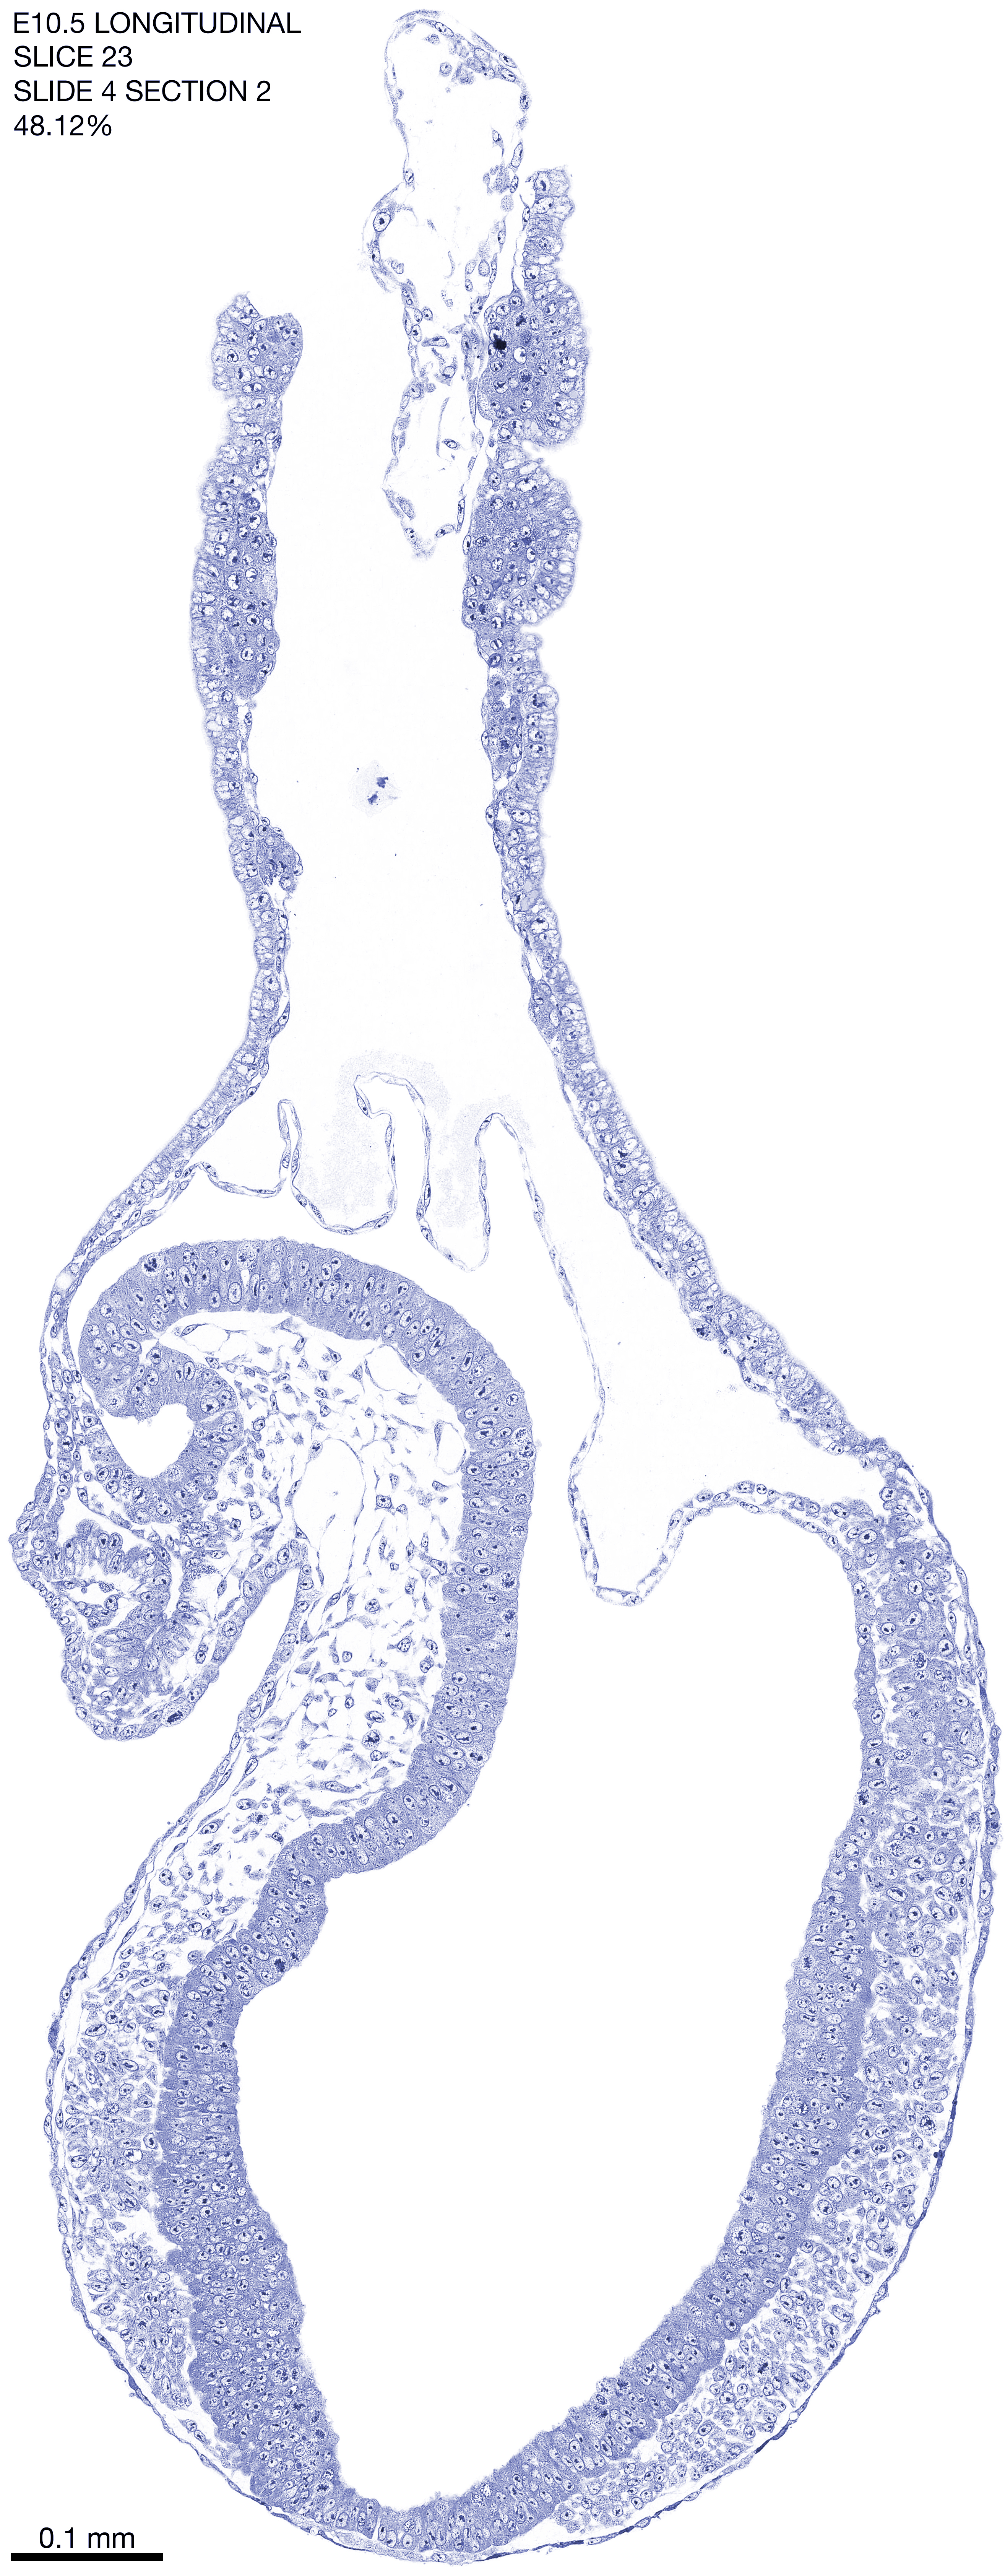

E10.5 Longitudianal Archive This page contains jpg files of ALL SLICES (each 3µm thick) that were scanned of the E10.5 longitudinally cut specimen. Download: Large | High Res Download: Large | High Res Download: Large | High Res Download: Large | High Res Download: Large | High Res Download: Large | High Res Download: Large | High Res Download: Large | High Res Download: Large | High Res Download: Large | High Res Download: Large | High Res Download: Large | High Res Download: Large | High Res Download: Large | High Res Download: Large | High Res Download: Large | High Res Download: Large | High Res Download: Large | High Res Download: Large | High Res Download: Large | High Res Download: Large | High Res Download: Large | High Res Download: Large | High Res Download: Large | High Res Download: Large | High Res Download: Large | High Res Download: Large | High Res Download: Large | High Res Download: Large | High Res Download: Large | High Res Download: Large | High Res Download: Large | High Res Download: Large | High Res Download: Large | High Res Download: Large | High Res Download: Large | High Res Download: Large | High Res Download: Large | High Res Download: Large | High Res Download: Large | High Res Download: Large | High Res Download: Large | High Res Download: Large | High Res Download: Large | High Res Download: Large | High Res Download: Large | High Res Download: Large | High Res Download: Large | High Res Download: Large | High Res Download: Large | High Res Download: Large | High Res Download: Large | High Res Download: Large | High Res Download: Large | High Res Download: Large | High Res Download: Large | High Res Download: Large | High Res Download: Large | High Res